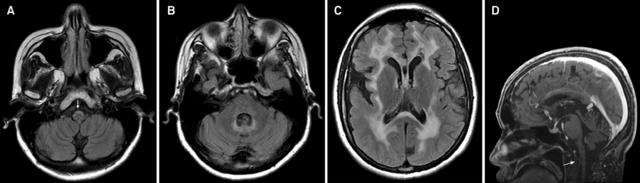

图 9 T2WI 可见明显的延髓萎缩 [a] 伴轻度小脑萎缩 [a~b],但脑桥基底部基本正常 [b],四脑室稍扩大 [b],中脑,特别是背侧,可见萎缩 [c];l:矢状位 T1WI 可见典型的蝌蚪状脑干萎缩,包括明显的颈髓-延髓萎缩,脑桥基底部完整,需注意,中脑被盖萎缩同样促成了「蝌蚪」的形成

图 14 A~B:T2WI 可见小脑深部白质,小脑中脚和脑桥高信号病灶;C~D:FLAIR 提示脑室旁和皮质下白质以及胼胝体压部弥漫高信号伴萎缩;亦可见内囊 [C] 和脑桥 [B] 皮质脊髓束高信号 [箭头]